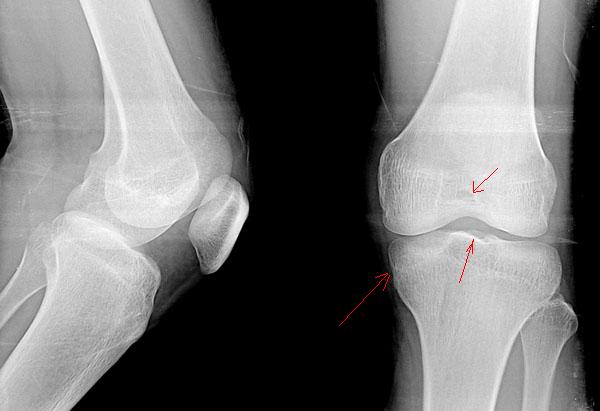

标题: X4122:男 20岁 活动时感觉关节内有东西,活动时疼痛。箭头 [打印本页]

男 20岁  活动时感觉关节内有东西,偶尔疼痛。箭头指的地方有问题吗?

不排除胫骨平台内游离骨片

膝关节正侧位平片未见明显异常。必要时请做ct进一步检查。

关节间隙好窄,mr进一步检查吧!